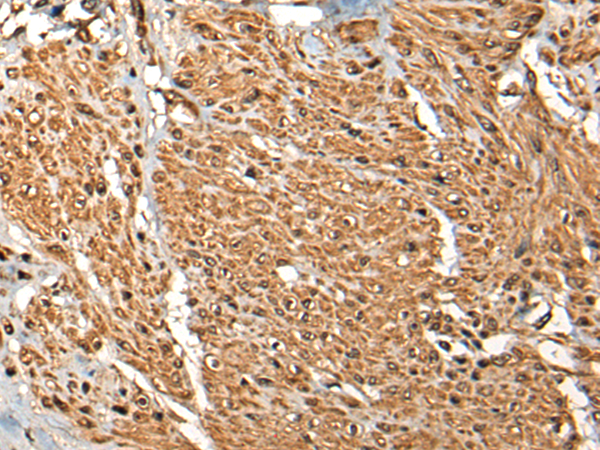

分类: 科研抗体货号: P02388别名: LGS应用: IHC反应种属: Human, Mouse